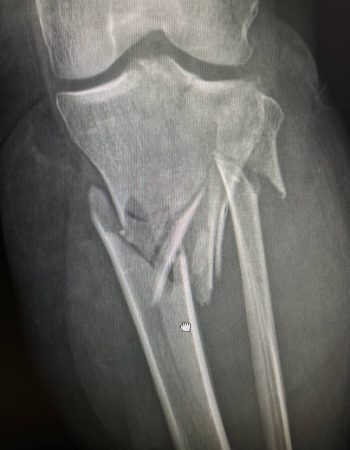

Під час обстежень було діагностовано багатоуламковий перелом в/3 лівої гомілки.

На момент поступлення у пацієнтки наявні симптоми розвитку компартмент-синдрому, це стан при якому набряк мʼяких тканин настільки сильний, що вони починають здавлювати самі себе, що може призвести до важких ускладнень в тому числі і ампутації . Тому при поступленні пацієнтці було проведено ургентну операцію – стабілізацію перелому апаратом зовнішньої фіксації та фасціотомію.